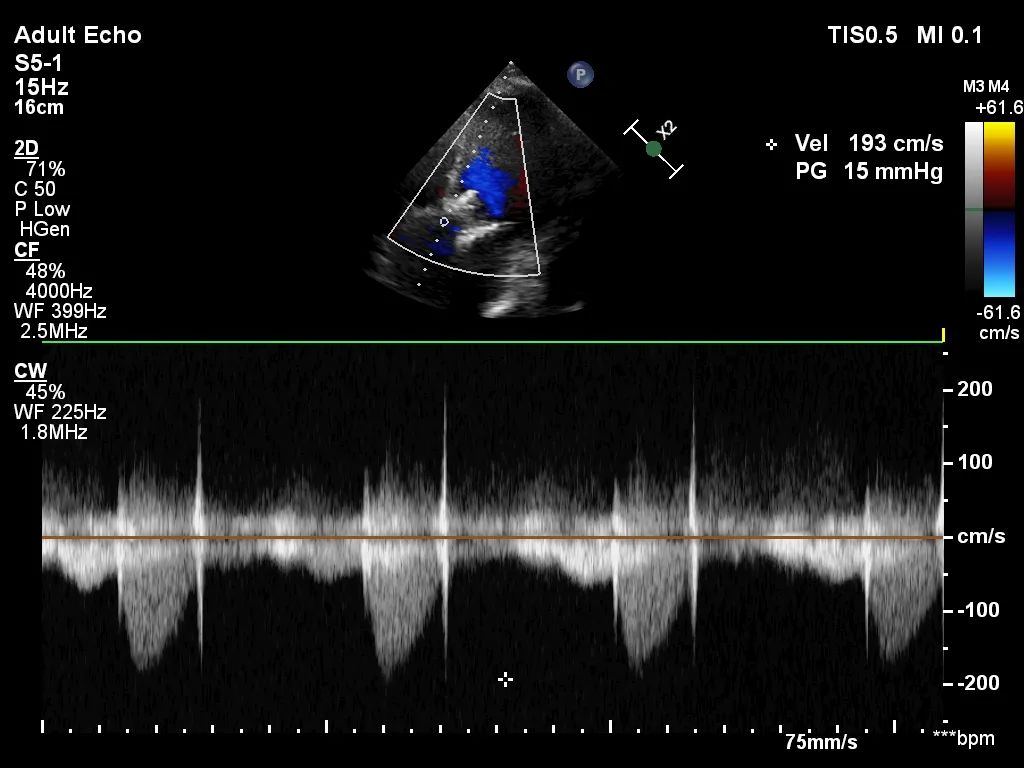

6. 回收后进行重新定位释放,释放完毕后超声评估示平均跨瓣压差15mmHg,超声、造影评估示中量瓣周漏、少量瓣中漏,瓣膜整体下滑明显,遂行瓣中瓣策略;

8. 扩张后跨瓣压差降至8mmHg,造影示轻微瓣周漏,患者血流动力学指标改善明显,手术圆满成功。